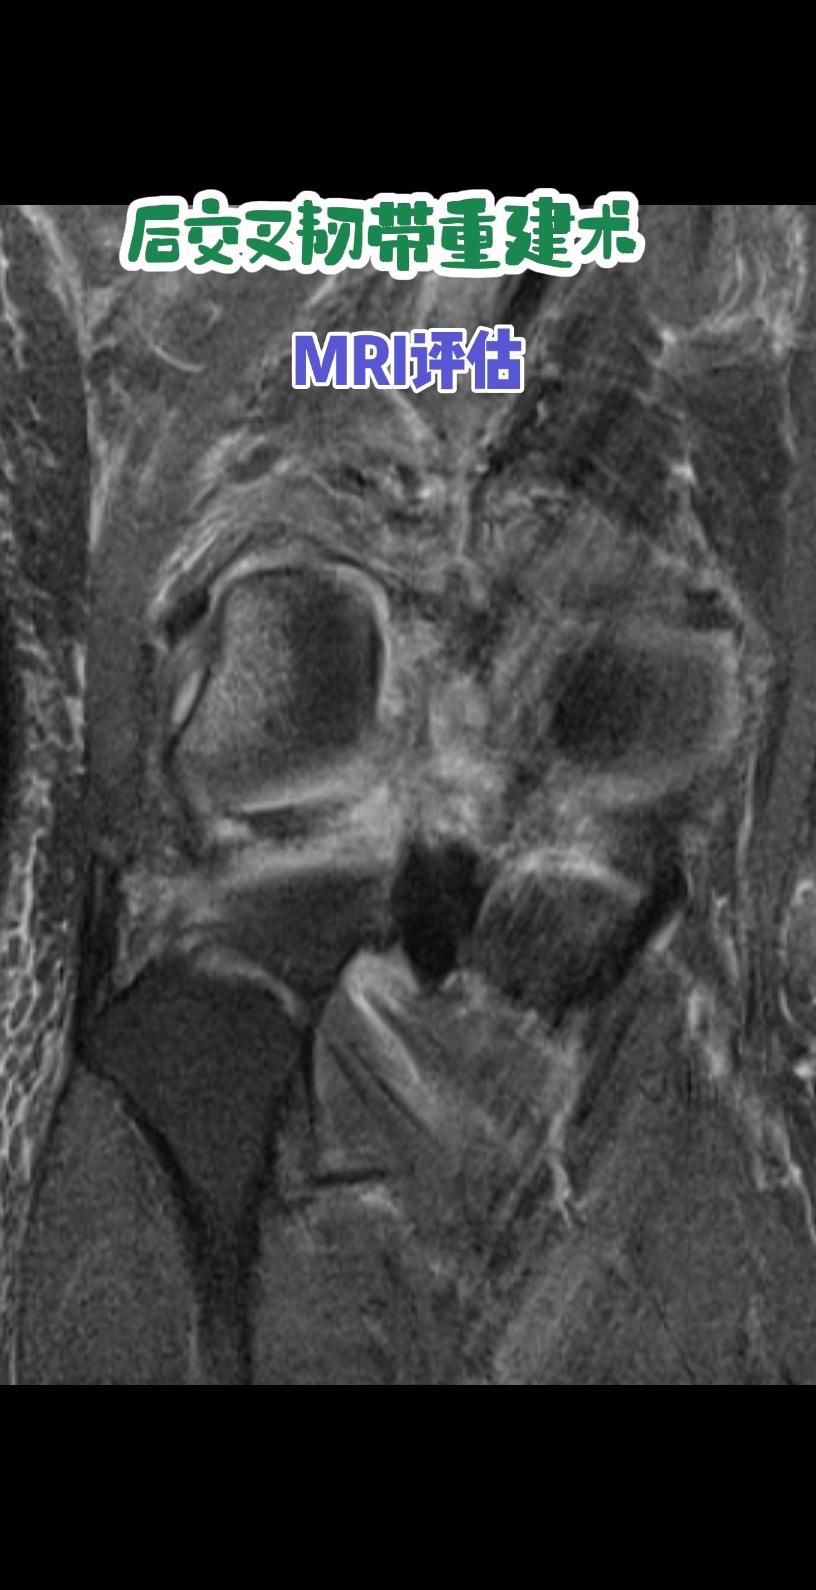

后交叉韧带重建术后影像评估。每一条韧带,都是膝盖的隐形安全带。而精准重建,就是给关节最可靠的浪漫守护。